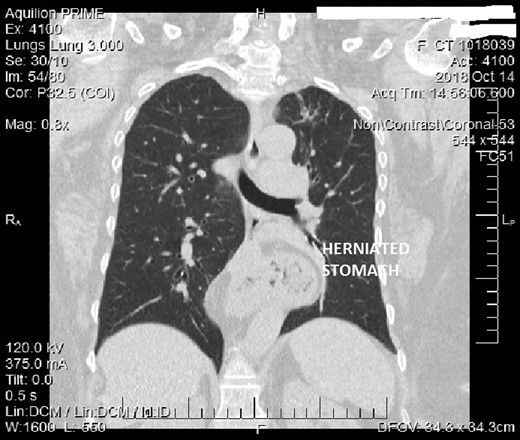

A 63-year-old woman with a height of 161 cm and weight of 116 kg (BMI 44.8 kg/m2) presented with progressive dyspnea, mostly present when bending over, coughing, belching, regurgitation and pyrosis. Medical history revealed hysterectomy 30 years back and hypertension since 10 years. Besides her morbid obesity, there were no other findings revealed by physical examination. CT scan revealed a mixed sliding and paraesophageal hernia, with almost half stomach in the chest (type 4 hiatal hernia) with cholilithiasis (Fig. 1). All relevant investigations, PAC and physician clearance was done. Benefits and risk factor of the surgery were explained and consent for laparoscopic / open haital hernia repair with cholecystectomy with RNYGB taken.